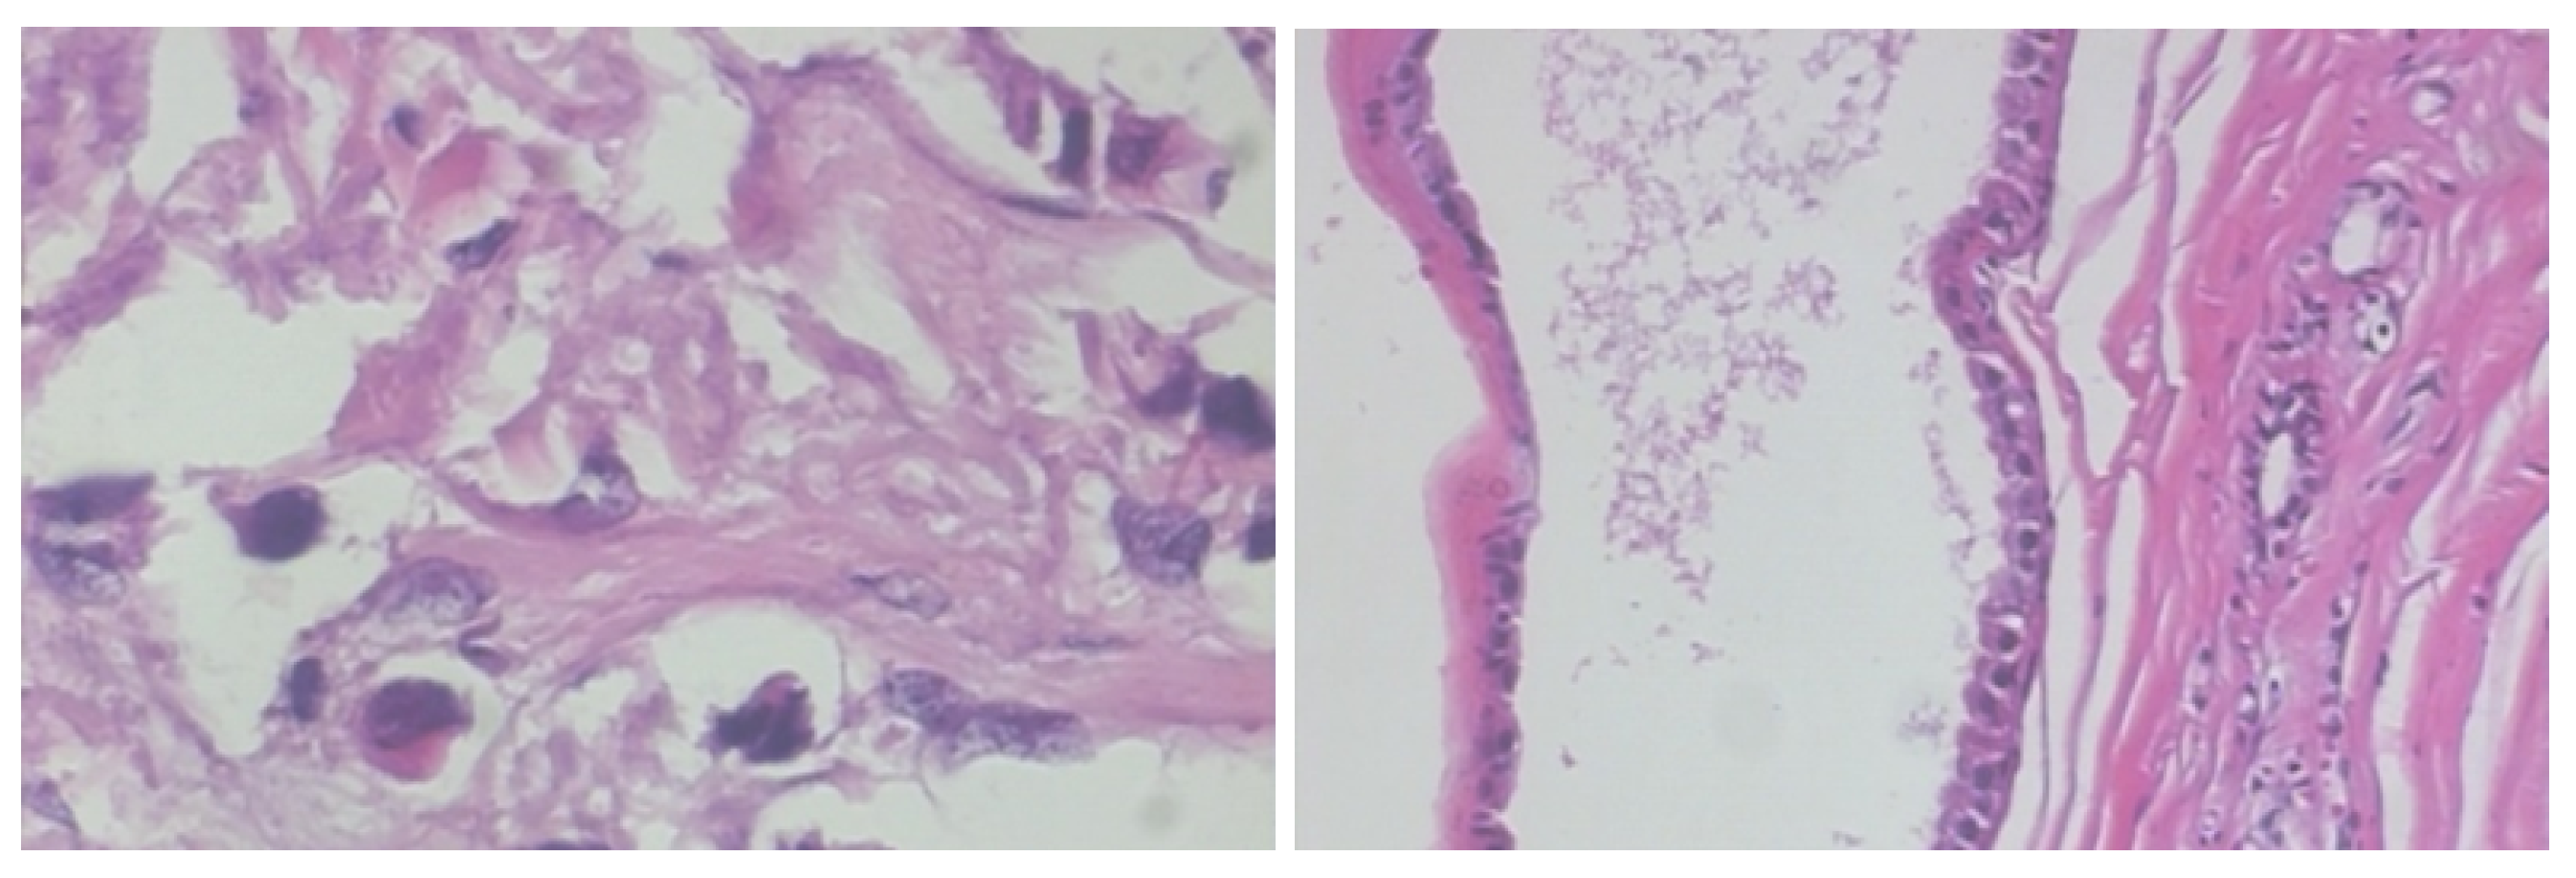

2.1. BreakHis Breast Cancer Histopathological Image Dataset

3.1. Step 1: Histopathological Image Pre-Processing